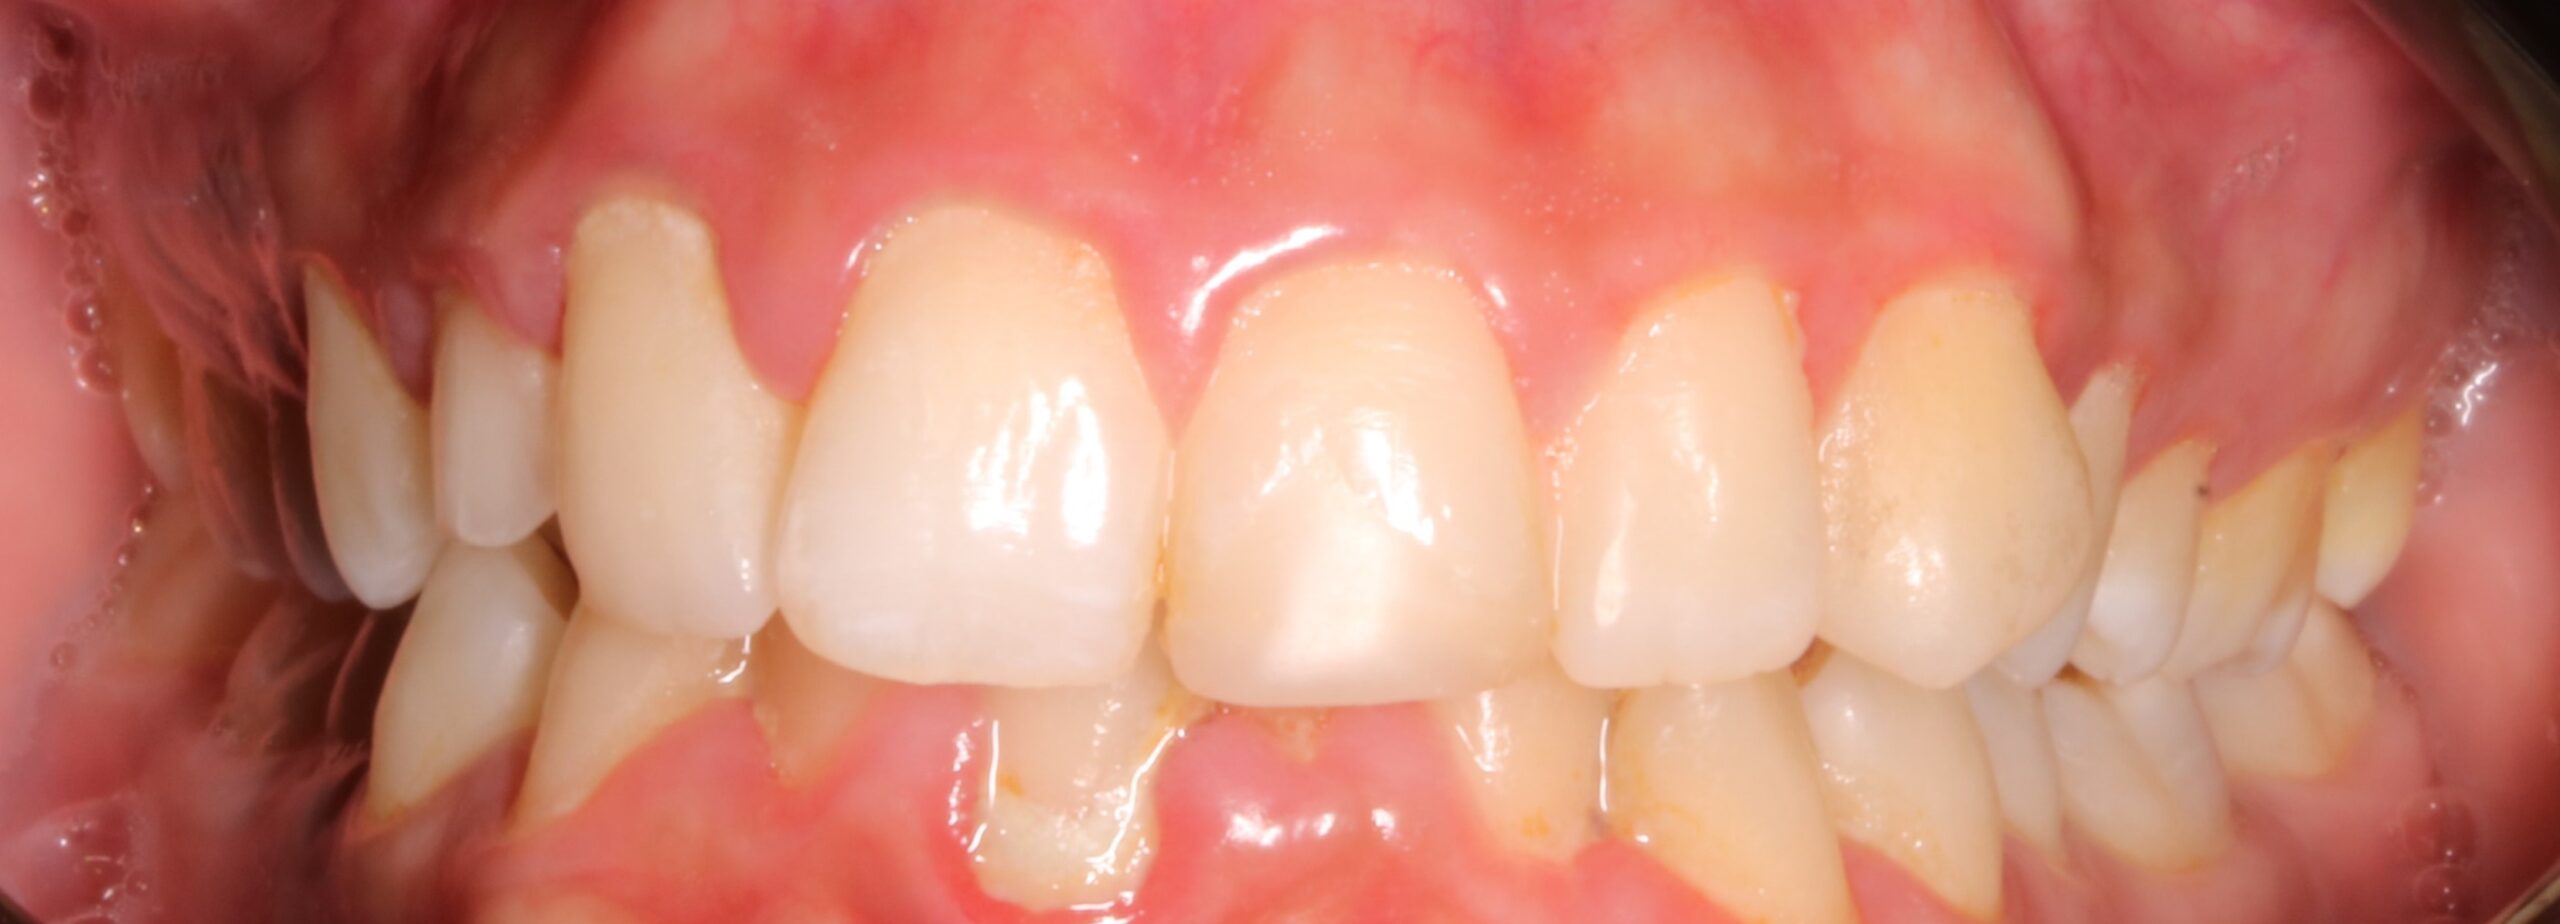

Como principal escollo, nos encontramos con una activa enfermedad periodontal y una deficiente higiene oral. También hay otros problemas secundarios que no hay que desdeñar: apiñamiento inferior con Bolton; leve apiñamiento anterosuperior; malposición de los cordales 48 y 38; rotación del 23; ligera clase II en el lado derecho entre otros. De primera hora se le comunicó a la paciente que antes de empezar el tratamiento de ortodoncia era necesario realizarse de periodoncia, y que después el/la profesional de esta disciplina, nos confirmara que podíamos empezar nuestro trabajo. También, avisamos de la importancia, de que durante el tratamiento, era necesario acudir al periodoncista cada 2 meses y mejorar la higiene oral.

CLASE II LEVE GOMAS CLASE 2 LEVE

FOTOGRAFÍAS DE INTERÉS